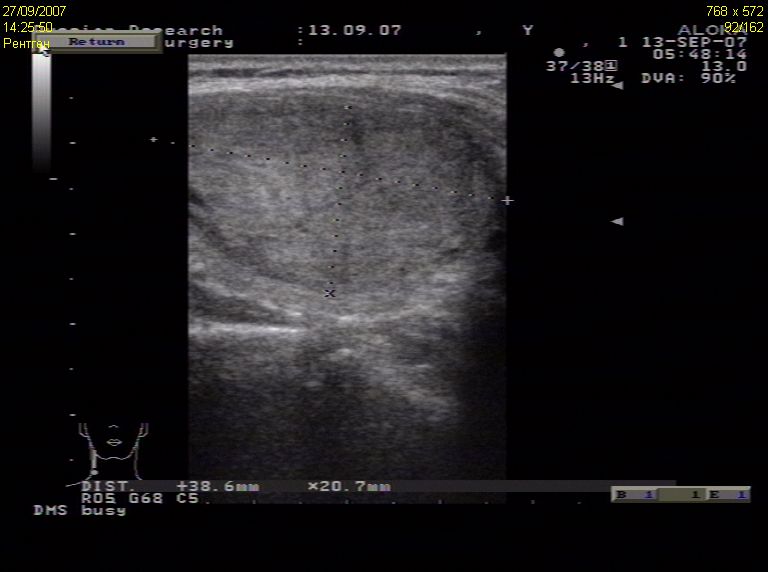

TI-RADS 5. Солидные узлы с “большими” признаками злокачественности для выполнения ПУНКЦИИ:

- солидные узлы более 1,0 см в диаметре: при наличии хотя бы одного “большого” признака злокачественности (рис. 4):

– значительно сниженная эхогенность;

– вертикальная пространственная ориентация образования;

– неровный контур образования: бугристый, микродольчатый, лучистый;

– наличие в опухоли микрокальцинатов;

Рис. 4. TI-RADS 5. Узлы ЩЖ размером >1,0 см (папиллярные раки): а, б – узлы значительно пониженной эхогенности с микрокальцинатами, с неровными микродольчатыми контурами; в – узел вертикальной пространственной ориентации, с нечеткими, неровными контурами, значительно сниженной эхогенности, с множественными микрокальцинатами; г – узел с микродольчатыми нечеткими контурами, неравномерно пониженной эхогенности, с микрокальцинатами; д – узел значительно пониженной эхогенности, вертикальной пространственной ориентации, с нечеткими, неровными (лучистыми) контурами; е – узел с нечеткими контурами, с множественными микрокальцинатами.